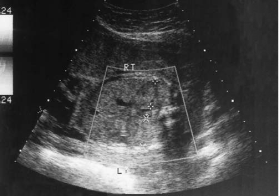

During a late second-trimester screening examination, what does this image of the fetal abdomen most likely show:

infantile polycystic disease

Which of the following conditions will likely occur because of this abnormality?

oligohydramnios